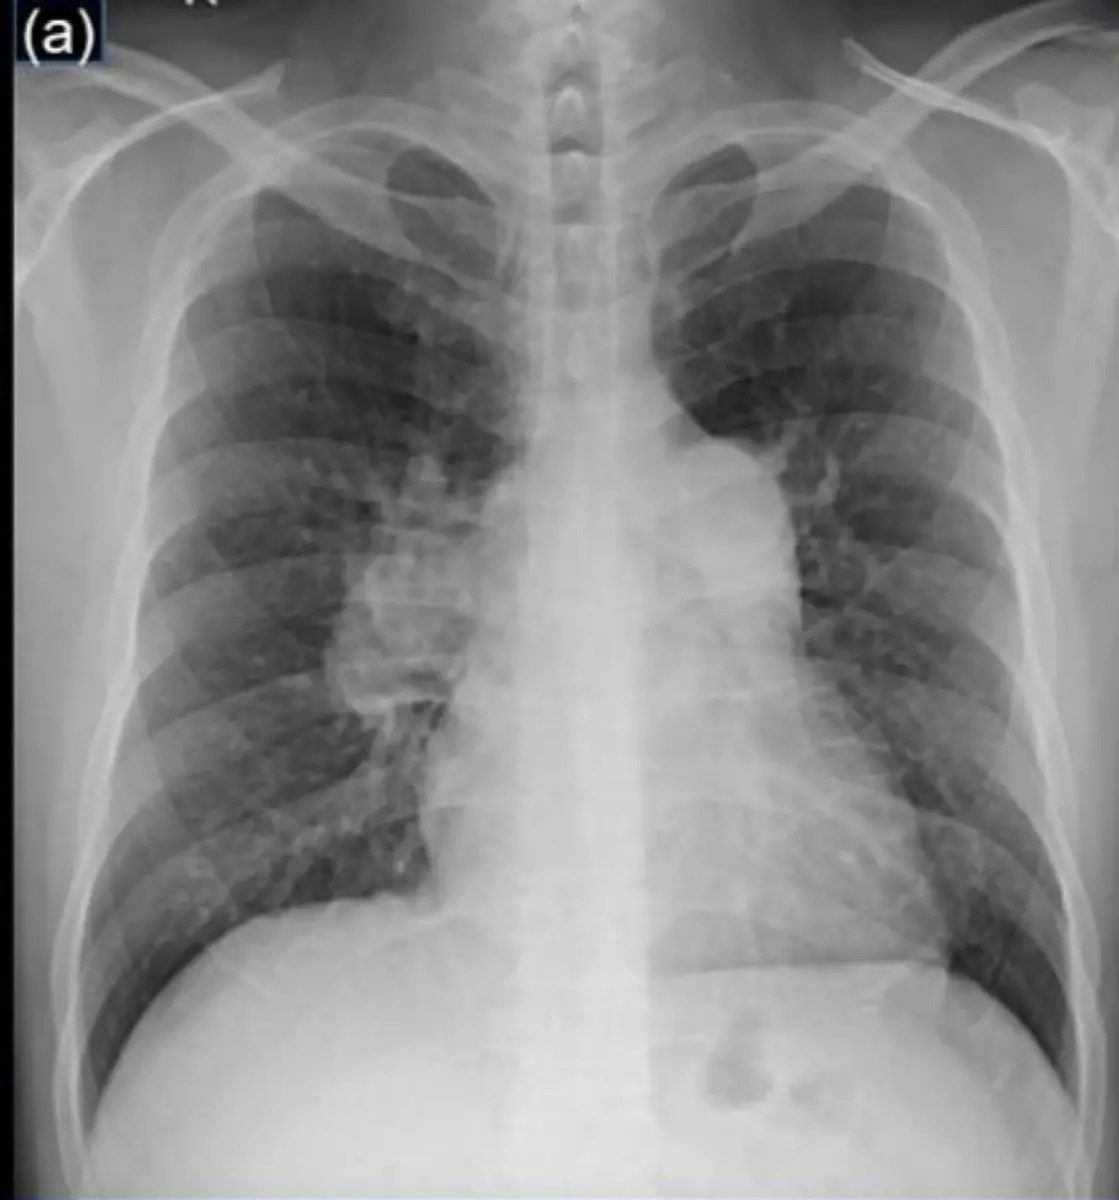

某47歲病人因呼吸困難就醫。胸部X光如圖所示。請問安排下列何種檢查最能確定其診斷?

本題核心圍繞 Pulmonary Hypertension (PH) 的放射影像特徵與確診流程。利用胸部X光初步偵測中樞肺動脈擴張、週邊血管修剪(pruning)及右心影增大等徵象後,透過 Transthoracic Echocardiography (TTE) 篩檢,再以 Right Heart Catheterization (RHC) 作為金標準確診並量化肺動脈壓。

從 PA 及側位胸部X光可見:

- 中樞肺動脈主幹及左右分支明顯擴張;右降支肺動脈外徑估計超過男性標準16 mm,符合肺動脈壓升高表現(pmc.ncbi.nlm.nih.gov)。

- 週邊小血管顯著修剪,肺野末梢血管消失,顯示中樞血流過度集中文段,典型 Pulmonary Arterial Hypertension 影像特徵(learningradiology.com)。